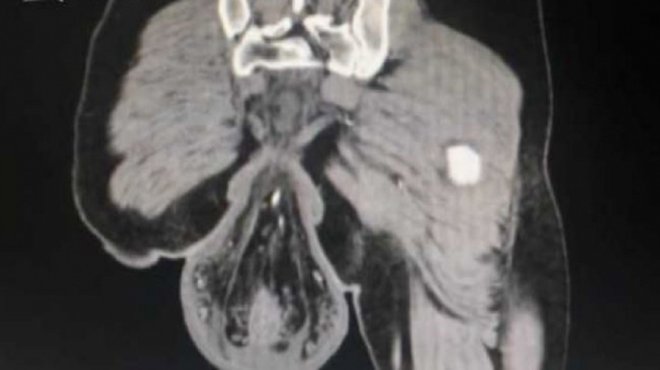

博士針對這現象警告,長期坐在馬桶會對直腸和肛門造成壓力,進而導致痔瘡、肛裂,甚至會有直腸脫垂的問題,小心上廁所上到一半掉出來的不是大便!

大腸直腸外科陳威佑過去也分享直腸脫出的應對方式,指出直腸脫垂的情況很少一下子就整個脫出,起初直腸可以自動縮回,直到情況變嚴重才會頻繁脫出,如果用手都推不回去就要靠手術來處理了。